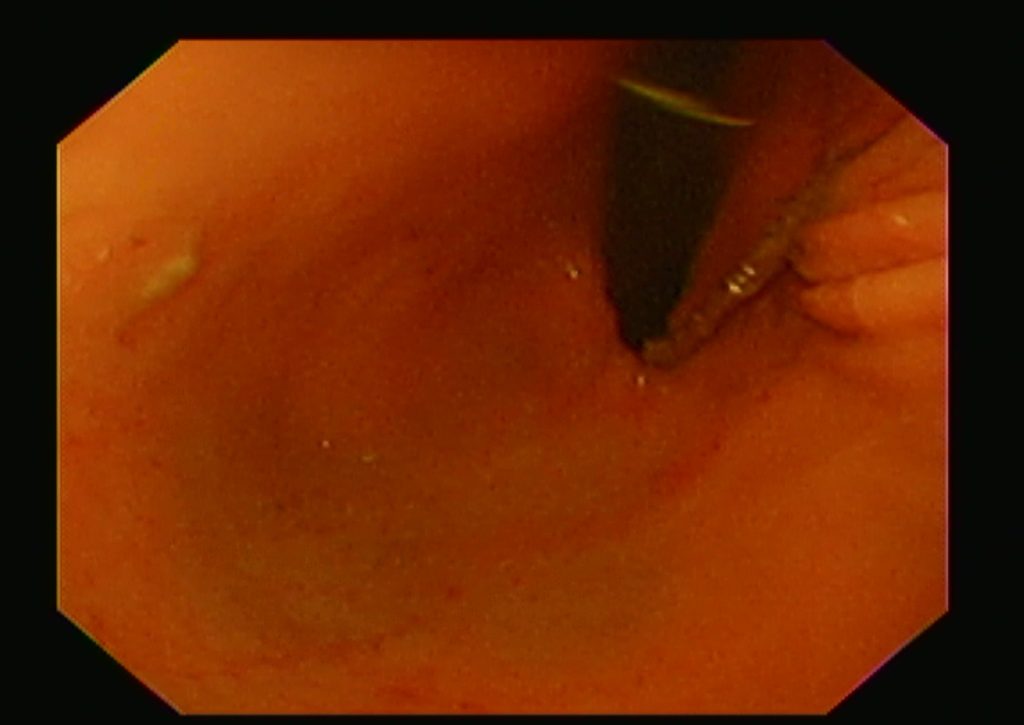

噴門(胃の入り口)の毛糸

胃の中へ